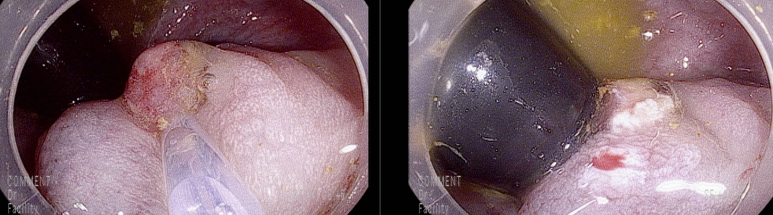

항문연 경계에 아래와 같은 13 mm 크기의 경이 있는 용종

표면에 발적변화를 보았을 때 마찰에 의한 출혈점 가능성

두번에 걸쳐 용종 절제술 시행함